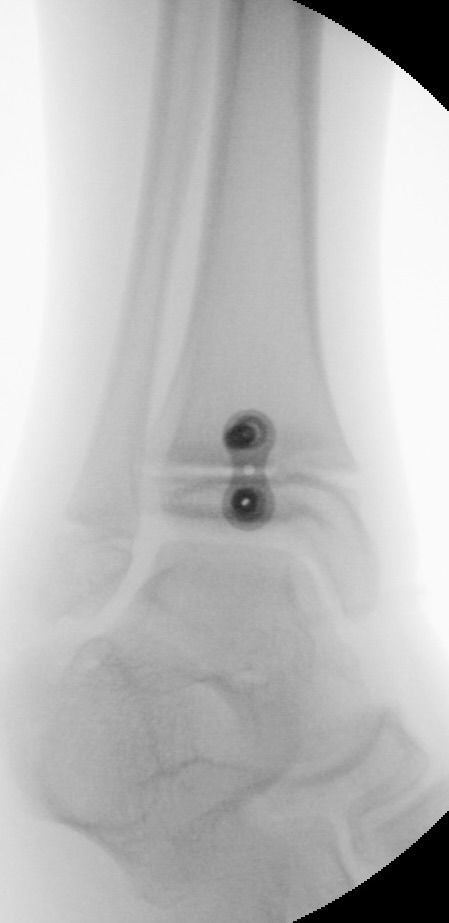

Abb. 8 a-g: Genua vara prä- und postoperativ versorgt mit Flex Tacks (a-b) und ein Genu valgum versorgt mit Eight Plate an der medialen Femurkondyle (c); Spitzfuß bei congenitalem Klumpfuß und einem Flat Top Talus mit präoperativem Röntgenbild seitlich und der deutlich nach dorsal stehender Tibia(d); intraoperative Bilder der Epiphysiodese mittels Eight Plate zur Wachstumslenkung der distalen Tibia in die Extension (e-f) und postoperativer Verlauf nach sechs Monaten mit regelrecht stehender Tibia über dem Talus durch die distale Extension (g).

Zum Lesen der Bildbeschreibung und zur Vollansicht bitte die Bilder anklicken. Bilder: A. Helmers.